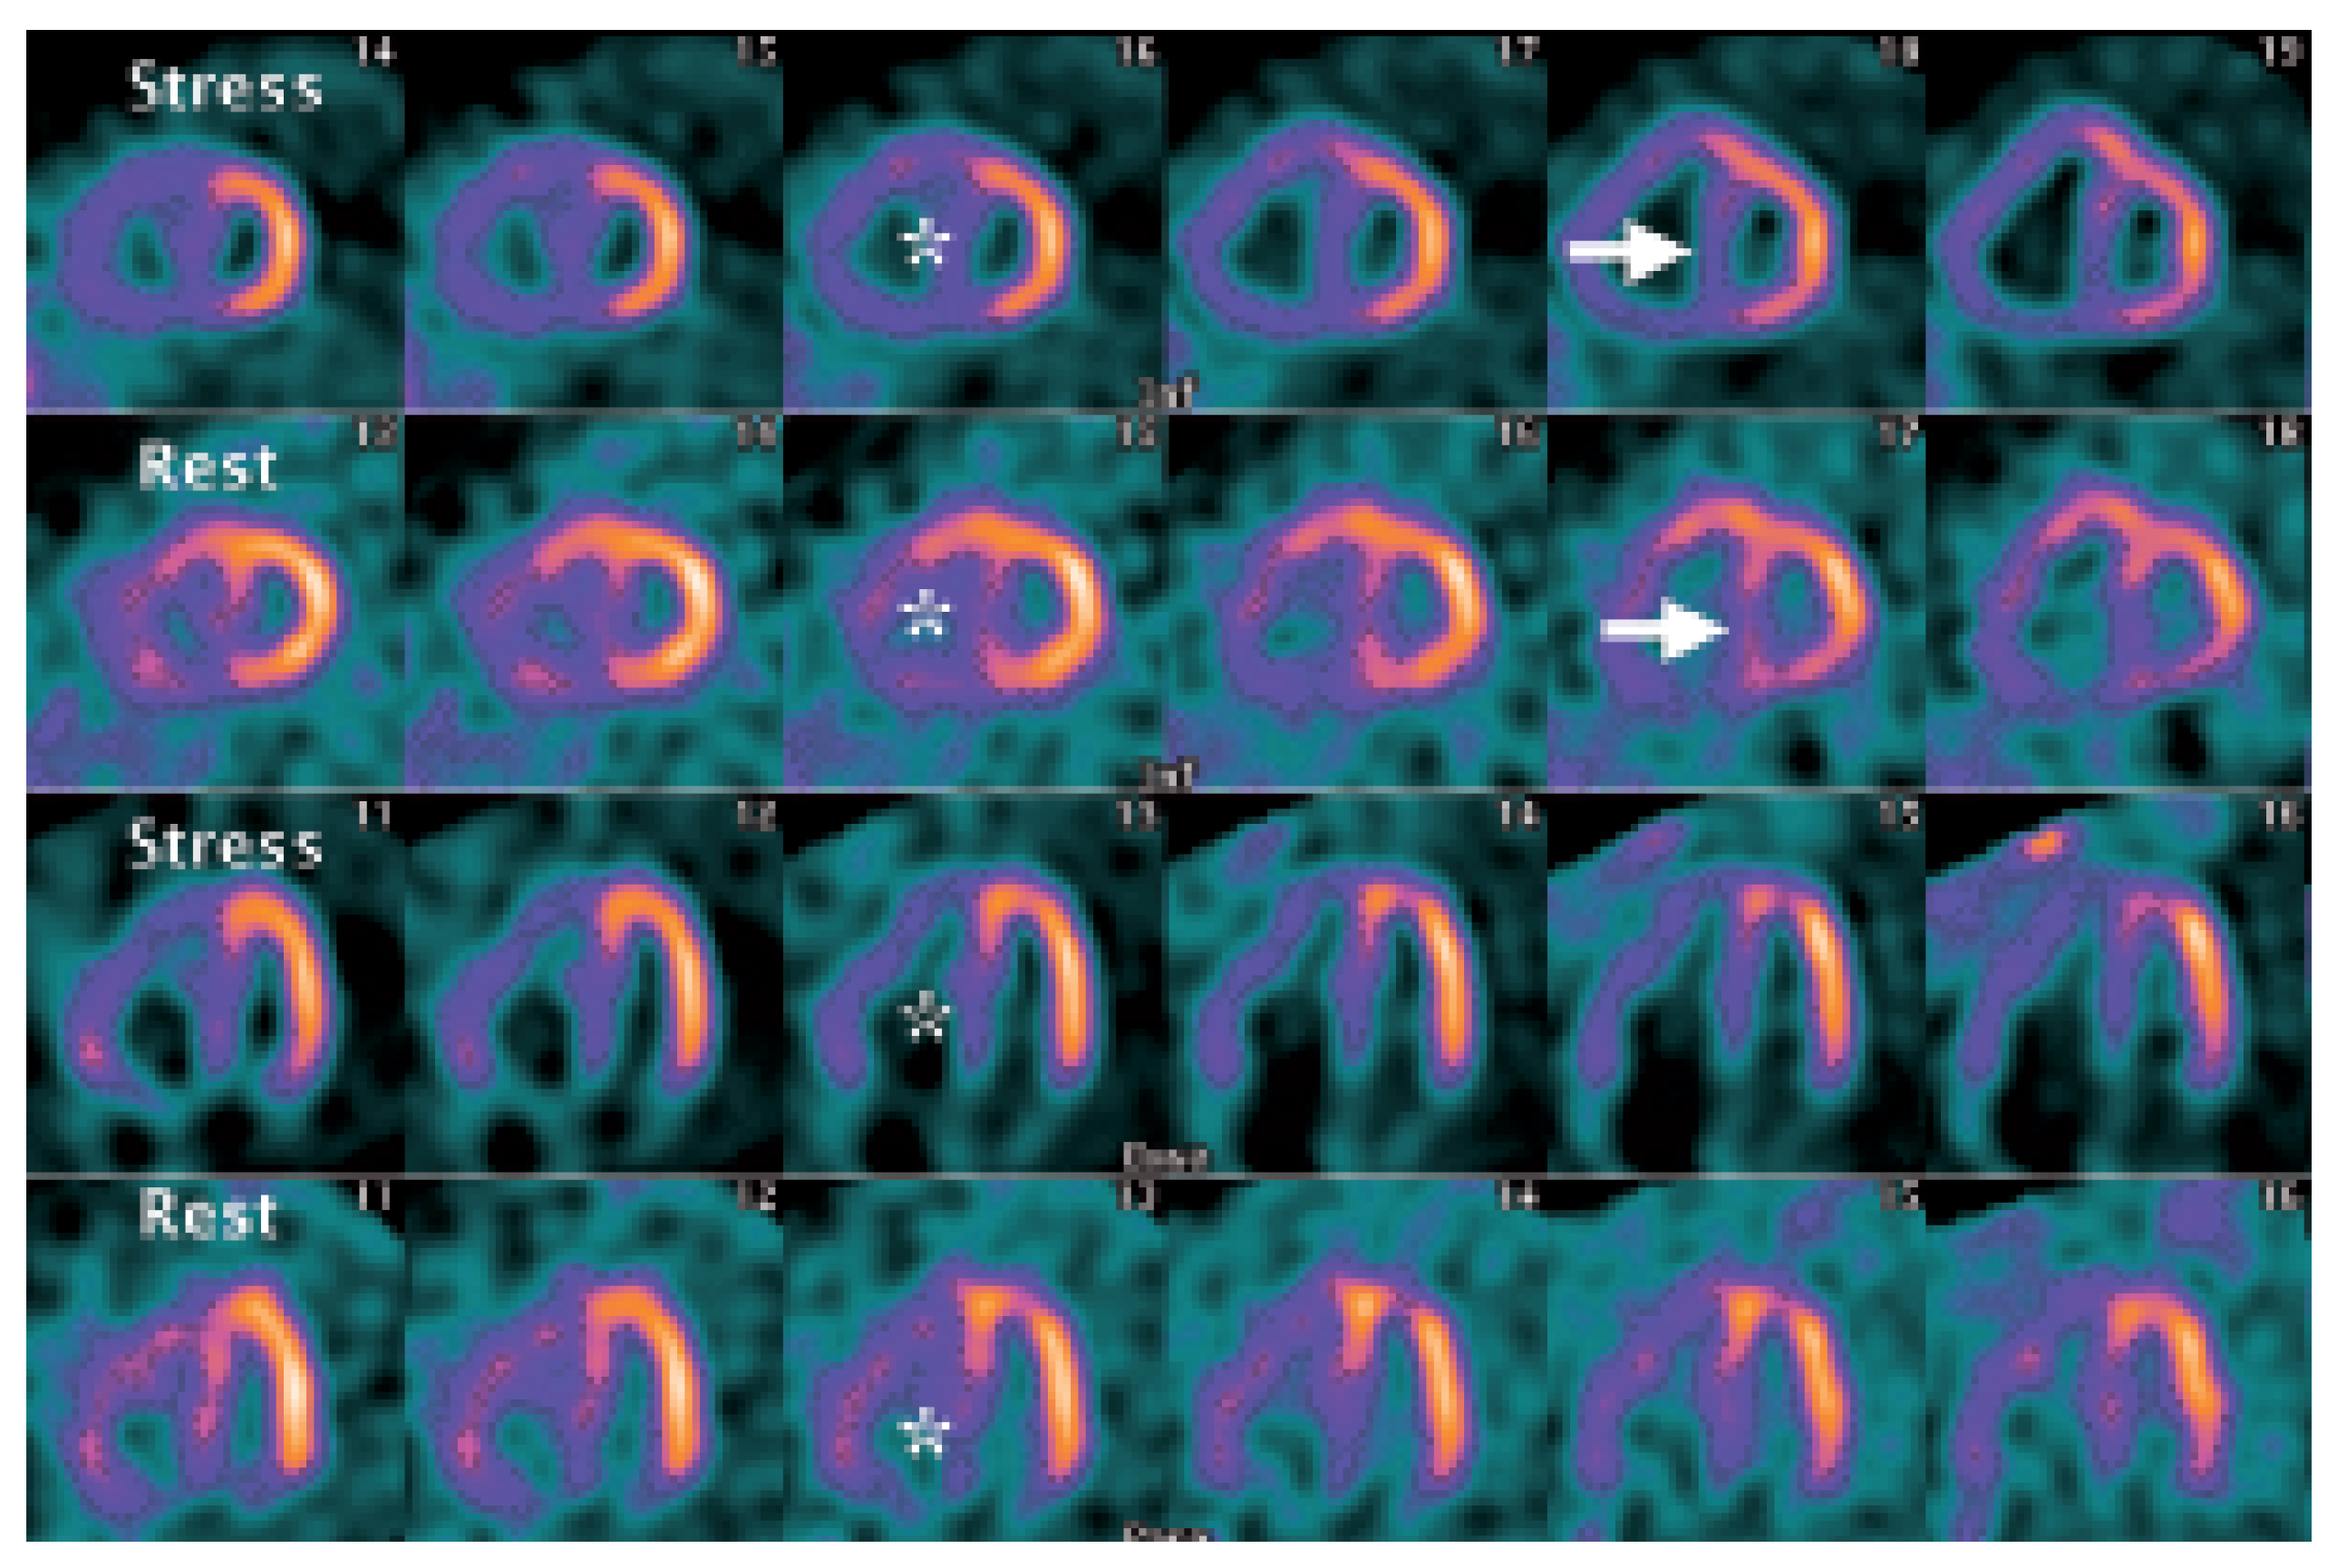

Myocardial Perfusion SPECT Features of Severe Pulmonary Artery Hypertension

Case Report

- Movahed, M.R.; Hepner, A.; Lizotte, P.; Milne, N. Flattening of the interventricular septum (D-shaped left ventricle) in addition to high right ventricular tracer uptake and increased right ventricular volume found on gated SPECT studies strongly correlates with right ventricular overload. J. Nucl. Cardiol. 2005, 12, 428–434. [Google Scholar] [CrossRef] [PubMed]

- Gibbons Kroeker, C.A.; Adeeb, S.; Shrive, N.G.; Tyberg, J.V. Compression induced by RV pressure overload decreases regional coronary blood flow in anaesthetised dogs. Am. J. Physiol. Heart Circ. Physiol. 2006, 290, H2432–H2438. [Google Scholar] [CrossRef] [PubMed]